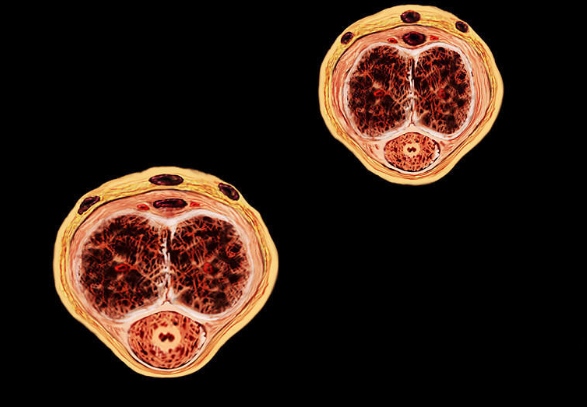

精索靜脈曲張圖片

精索曲張睪丸下墜時